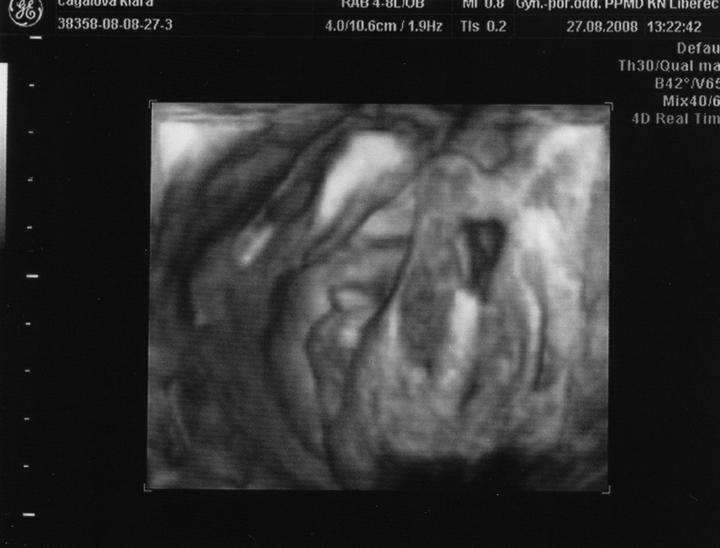

Doktor mi začátkem listopadu 2007 vysadil HA z důvodu zdravotních potíží,dávali jsme si tedy pozor a čekali,zda potíže ustoupí,ale 31.prosince 2007 mi manža řekl,že by chtěl miminko,byla jsem z jeho návrhu vykulená,ale byla to překrásná představa a tak jsem souhlasila..Od 8.ledna 2008 jsme se tedy začali snažit o miminko,začala jsem pít kontryhel a zobat Calibrum babyplan,aby mému tělu nic nechybělo 🙂 Nechávali jsme tomu volný průběh,ani jeden z nás na to nijak nepospíchal,nevím,proč jsem si říkala : Do roka se to snad povede 😀 A 29.3.2008 jsem měla pozitivní testík,sama jsem nechápala,jak brzy se to povedlo 🙂 Byla jsem neskutečně šťastná a stále jsem 🙂 Termín porodu dle MS 5.12.2008 a dle utz ve 12.tt 30.11.2008 Už od začátku jsem tušila,že čekám kluka a tak hned z první kontroly v 5.tt jsem si koupila modré bačkůrky pro štěstí,které se mnou chodili na každou kontrolu 🙂 Od 15.tt mi začalo celkem hodně tvrdnout břicho a chvilkama to bylo velice nepříjemné,na další kontrole,to jsem byla 18+4 , jsem to doktorovi řekla,ten mi pověděl,že se mu to vůbec nelíbí a tak mě poslal na utz,na utz jsem čekala 2 hodiny a můžu říct,že to byli nejhorší 2 hodiny v mém životě,tolik jsem se o miminko bála,ten strach,že něco není v pořádku byl opravdu k nevydržení..Přišla na mě řada a tak jsem tedy šla do kabinky a následně na lehátko na utz,pan doktor konstatoval,že všechno vypadá v pořádku a že se nemám bát,předepsal mi magnezium a že by to mělo pomoct,navíc koukám na ten utz a povídám panu doktorovi,to co tam vidím jsou kouličky? 😀 A on že jistě,že si myslel,že už to dávno vim,když se tak krásně ukazuje 😀 ,můj doktor mi řekl,že zřejmě porodím předčasně,což mě celkem vyvedlo z míry..Ale jsem optimisticky naladěnej človíček a tak jsem Honzíkovi vysvětlovala,že v bříšku musí ještě zůstat..Ve 20.tt jsem šla na velkej UTZ,kde mi opravdu řekli,že Honzík je zdravej a opět Honzík ukázal,že je 100% chlapeček 😀 Ve 26.tt jsme jeli na 4D utz do Liberce,tam se Honzík ukázal zas,no za celé těhu se nestalo,že by se na utz neukázal aa neroztáhl nožičky,máme malýho exibouše 😀 Ve 30.tt mě čekal další UTZ,vše v pořádku,Honzík už byl hlavičkou dolů a vážil 1600g ..Ve 35.tt mě doktor opět kvůli tvrdnutí břicha poslal už do ambulance,aby se o mě starali už tam.. Ten den jsem strávila v nemocnici 7hodin,fakt děsný !!! 2 hodiny čekání u mého doktora,ten mě tedy poslal už do nemocnice,takže jsem musela na UTZ,tam jsem čekala 2 hodiny,pak na natáčky,tam jsem čekala hodinu a pak na ambulanci a tak jsem čekala zas dvě hodiny ☹ Na UTZ ve 36.tt měl Honzík už 2600g ..